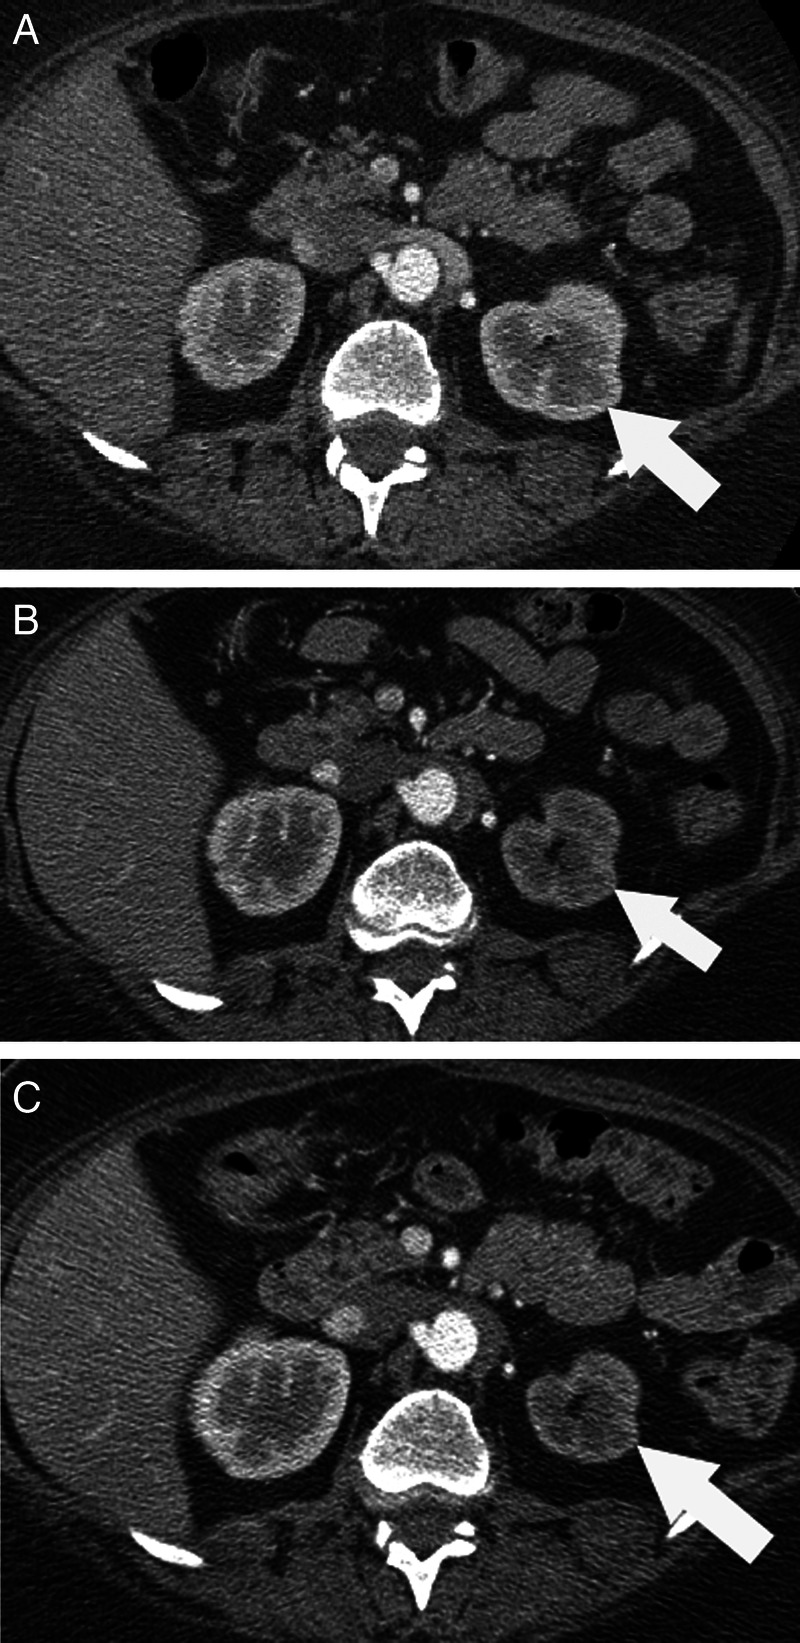

Figure 1.

(A) Axial abdominal CT images; prior to sorafenib treatment (A) the right and left kidneys showed similar size and enhancing characteristics on this corticomedullary phase abdominal CT (white arrow referring to left kidney). Twenty months on therapy (B), the left kidney (white arrow) showed delayed enhancement compared with the right, and there was selective loss cortical thickness. Twenty-four months on therapy (C), there was further left renal volume loss (white arrow) and grossly delayed and impaired contrast enhancement.